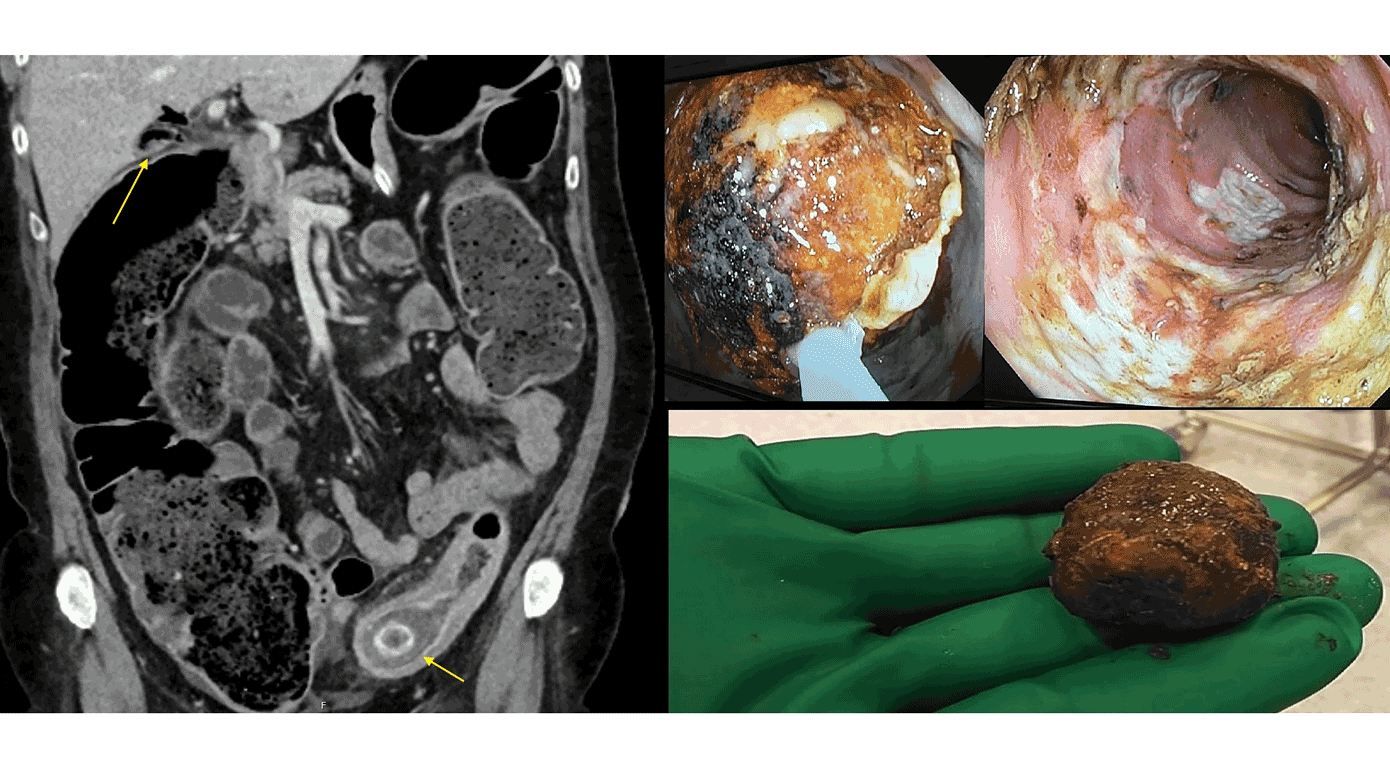

En 67-årig kvinde, der ikke tidligere var koloskoperet, blev indlagt grundet mavesmerter, afføringsstop og opkastninger. CT viste mekanisk colonileus med transitionszone svarende til en 4 cm stor galdesten indkilet i en kronisk divertikulitisstenose i sigmoideum, fistel mellem galdeblæren og højre colonfleksur samt luft i galdevejene (A).

Der blev indledt med mislykket endoskopisk stenfjernelse (B). Stenen kunne mobiliseres oralt i colon, og stenosen var skoppassabel uden malignitetstegn (C). Stenfjernelsen blev herefter udført ved laparotomi med kolotomi lige oralt for den relative divertikulitisstenose. Patienten blev udskrevet efter et ukompliceret postoperativt forløb til kontrolkoloskopi.